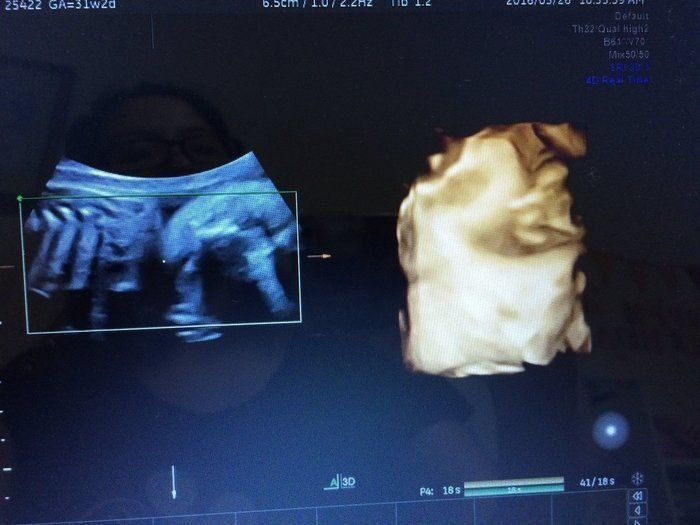

マダムまかろんさんの妊娠31週目のエコー写真 3Dエコー画像撮影に再チャレンジ

以前の3D画像撮影で赤ちゃんの顔の撮影ができなかったことがどうしても心残りで、義理の母が上京するタイミングに合わせて再撮影にチャレンジ。病院からは、この時期は赤ちゃんが育ちすぎているので希望通りに撮影できるかわかりません、と言われていました。それでも撮影中は、看護師さんが寝ている赤ちゃんをおなかの上から優しくゆすって顔の位置を変えてくれ、無事撮影することができました。